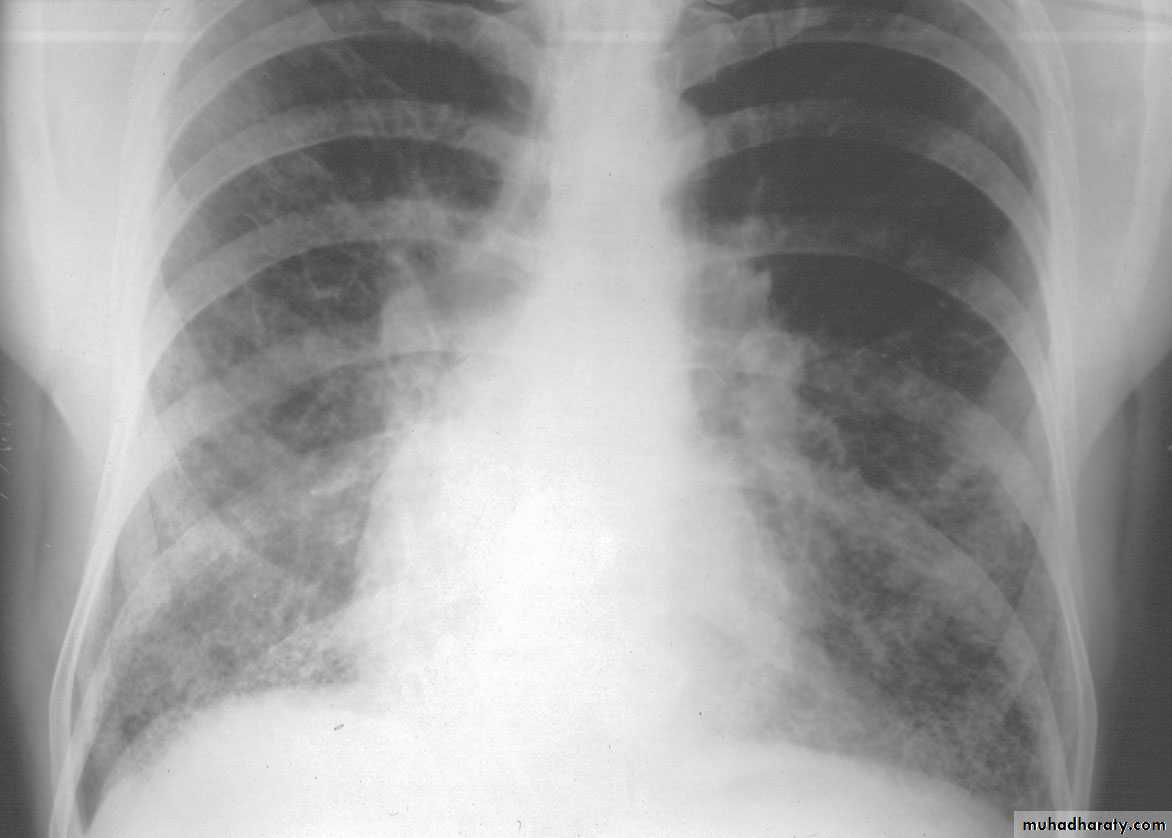

Acute bacterial pneumonias can present as one of two anatomic and radiographic patterns, referred to as bronchopneumonia and lobar pneumonia.1- Bronchopneumonia implies a patchy distribution of inflammation that generally involves more than one lobe . This pattern results from an initial infection of the bronchi and bronchioles with extension into the adjacent alveoli.

2-lobar pneumonia the contiguous airspaces of part or all of a lobe are homogeneously filled with an exudate that can be visualized on radiographs as a lobar or segmental consolidation Streptococcus pneumoniae is responsible for more than 90% of lobar pneumonias.